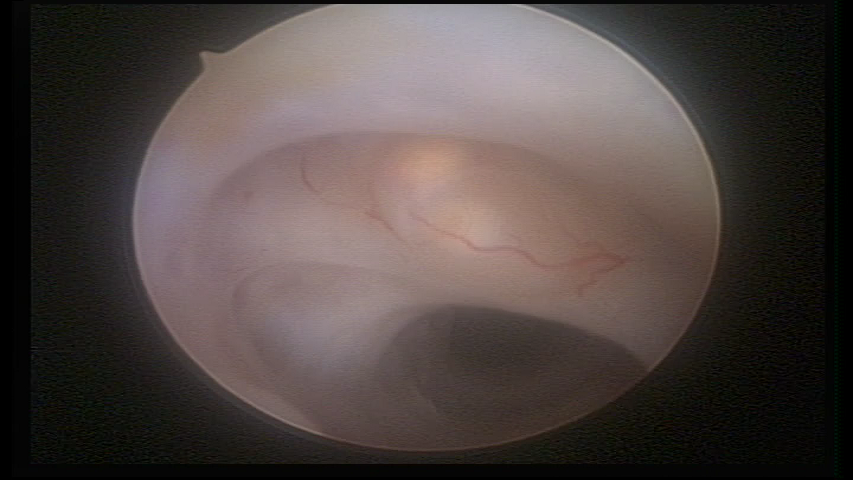

Retraction of a cesarean section scar with a non-absorbable suture for 30 years panoramic view